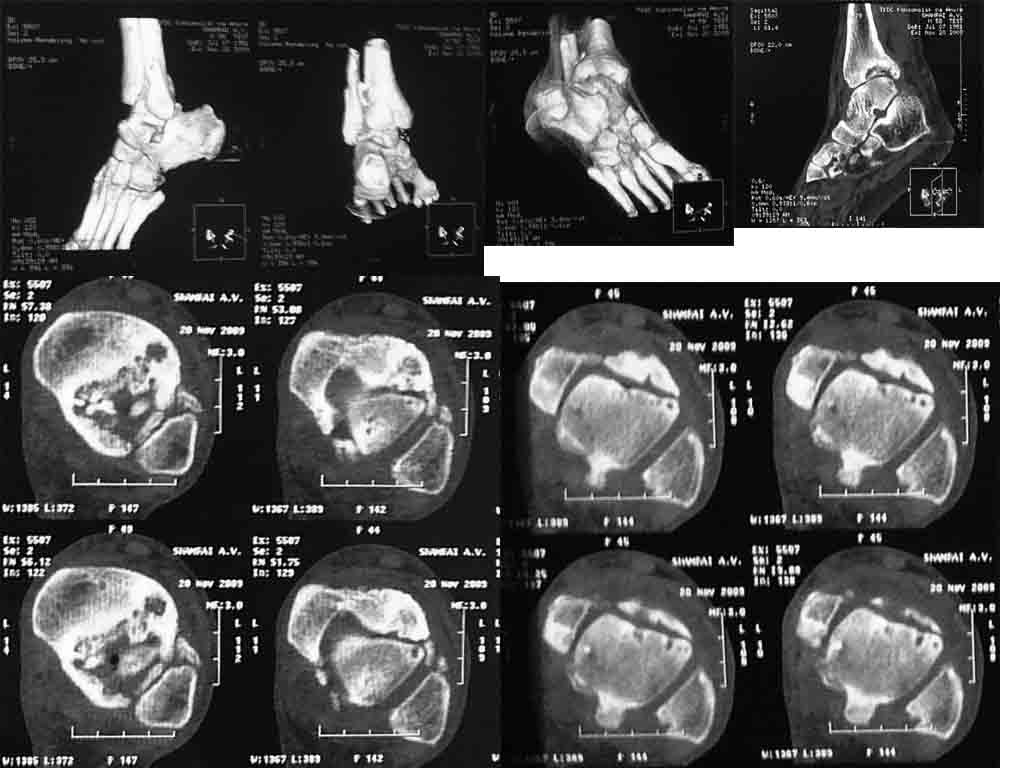

посттравматический асептический некроз

травма 2007 г., лечение консервативно прошу помощи в выборе оперативного пособия.

пациент 58 лет, соматически стабилен, платёжеспособен.